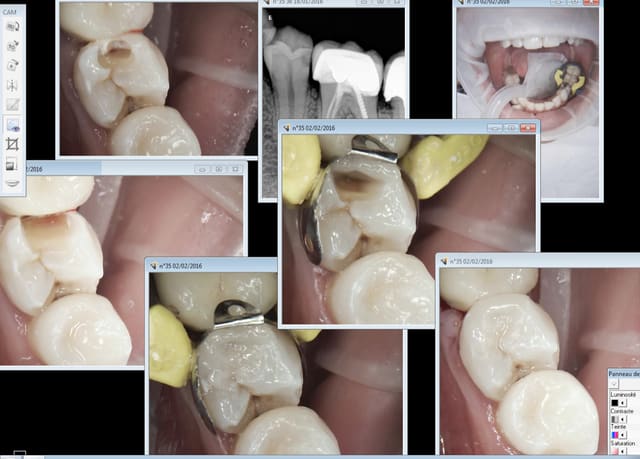

Capture_d_e_cran_2016-02-02_18.45.40_x6qesp.png